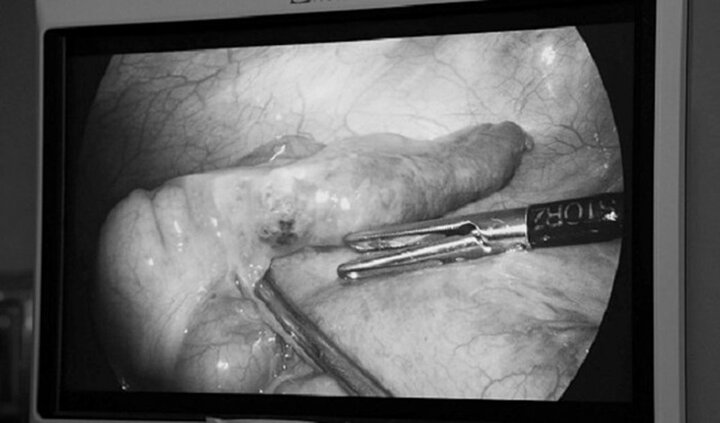

Trong lúc phẫu thuật cắt bỏ phần ruột thừa bị viêm của nam thanh niên, các bác sĩ phát hiện có mảnh xương cá đâm thủng một phần ruột của anh này.